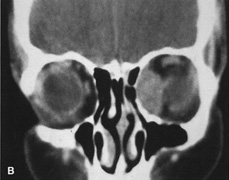

Valuable information about the nature and extent of an orbital pathologic process is provided by imaging studies such as computed tomography (CT) scan, magnetic resonance imaging (MRI), and orbital echography. Better spatial resolution, ready accessibility, and lower cost make CT the preferred choice for orbital imaging in most cases. Orbital fat provides a natural contrast between most adjacent orbital structures on CT scanning, and orbital bones are visualized well. Computed tomography is essential for evaluation of the orbital bones because they cannot be imaged with MRI. Direct coronal or sagittal images are important to identify the relationship of a lesion to the optic nerve so that the surgical approach can be planned to avoid traversing the optic nerve (Fig. 1).

Fig. 1. A. Axial CT scan demonstrating a large, well-encapsulated lesion in the orbital apex. Coronal (B) and sagittal (C) scans demonstrate that the mass lies inferior and medial to the optic nerve within the intraconal space. This information is useful in planning the surgical approach to the mass, which should avoid traversing the optic nerve.